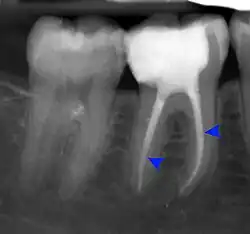

The periodontal ligament becomes inflamed and there may be pain when biting or tapping on the tooth. On an X-ray, bone resorption appears as a radiolucent area around the end of the root, although this does not manifest immediately.[10]: 228 Acute apical periodontitis is characterized by well-localized, spontaneous, persistent, moderate to severe pain.[6]: 125–135 The alveolar process may be tender to palpation over the roots. The tooth may be raised in the socket and feel more prominent than the adjacent teeth.[6]: 125–135